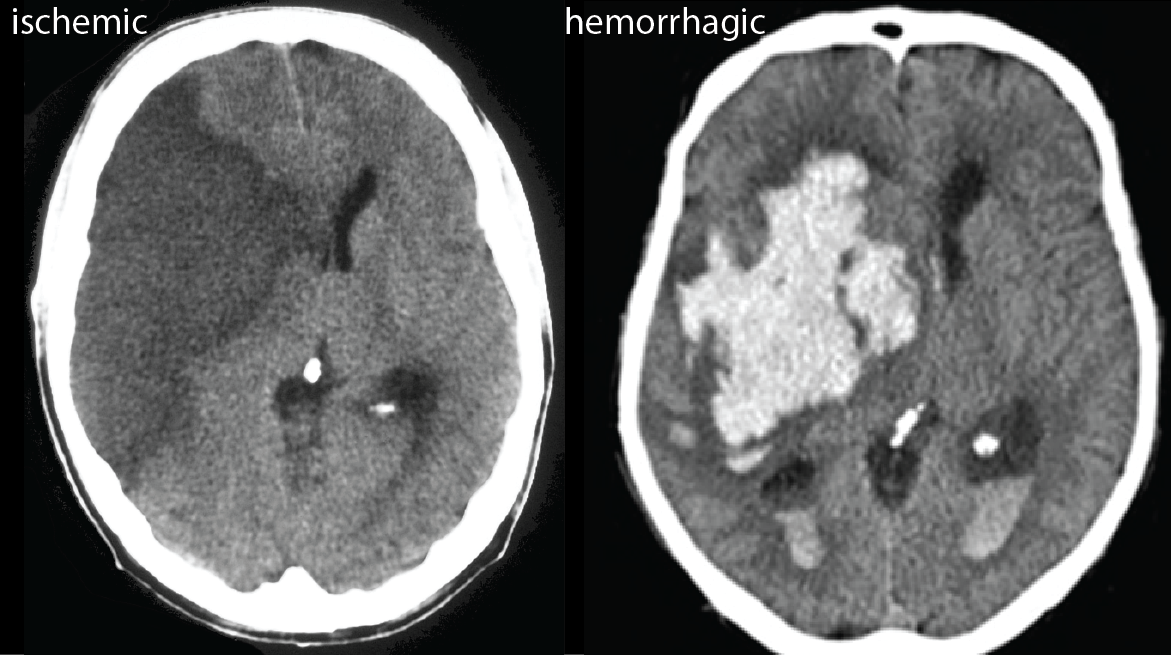

How do you distinguish between ischemic vs haemorrhagic strokes on CT scans?

Ischemic: not visible early on → takes time to establish then becomes hypodense (dark)

Haemorrhagic: bright white area with mass effect